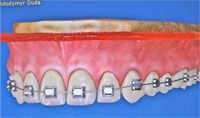

3. Ортодонтическая фиксация.

Если у Вас параллельно проводится ортодонтическое лечение (брекеты), можно фиксировать коронку к прямой дуге